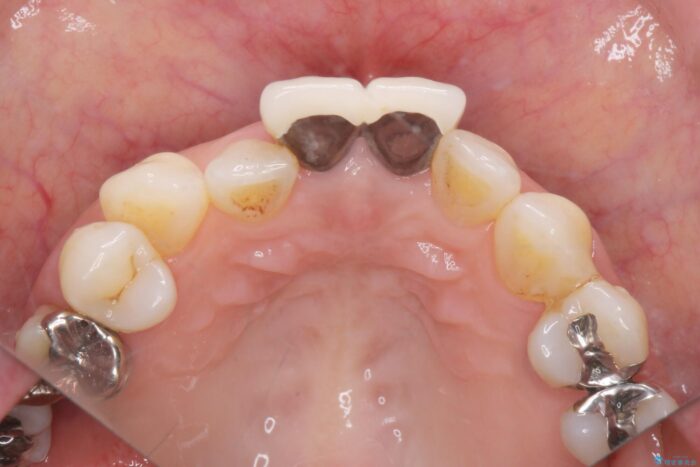

前歯の差し歯(クラウン)が黒ずんでいるとご相談にいらっしゃった患者様です。

根管治療は行わず、クラウンのやり替えのみ行います。

審美性に優れるジルコニアクラウンによる治療を計画します。